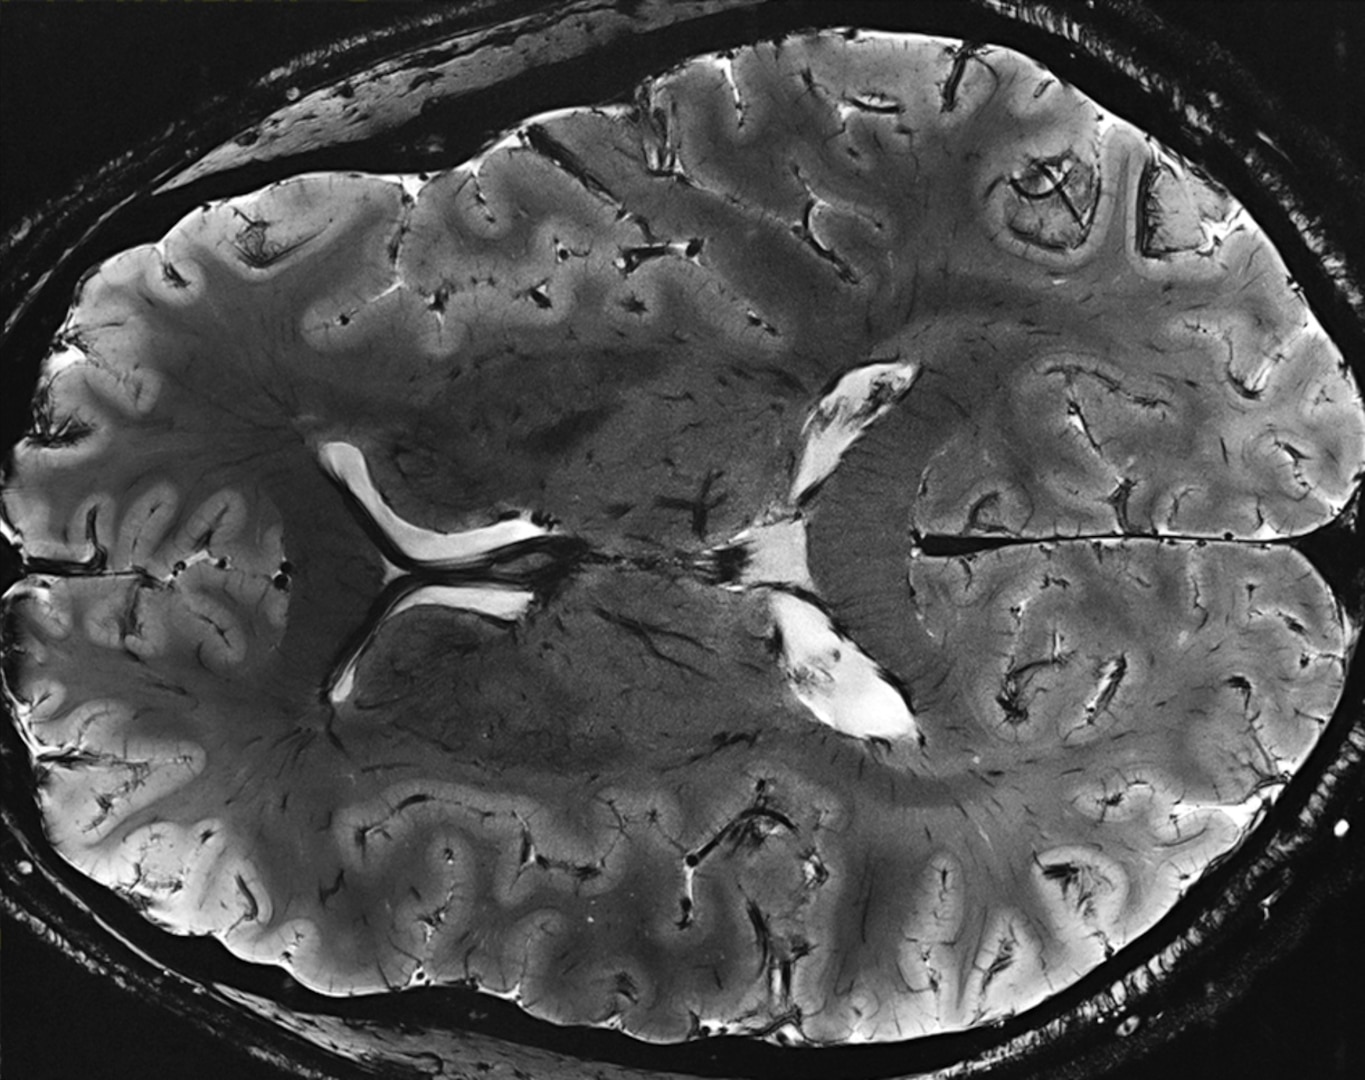

“This program has been a lifesaver for us in resurrecting a pioneering and extremely expensive federally funded MRI scanner,” said Jerome Ackerman, Ph.D., associate professor of radiology at Harvard Medical School and an investigator at the Athinoula A. Martinos Center for Biomedical Imaging at Massachusetts General Hospital. “We were unable to obtain sufficient liquid helium from our regular supplier, and did not know how we were going to get it.”

“The scanner has been out of operation since July following a quench of its magnet,” Ackerman said.

This occurs when the device suddenly loses superconductivity.

“Over 30 research projects, including one of my own, funded by the National Institutes of Health, make use of this scanner, so it is extraordinarily important to get it up and running again,” he said.

The startup of the MRI requires a large amount of helium packaged in dewars, or containers for liquified gases, because the hospital could not accept a bulk trailer load. The MGH/Martinos Center team working to secure liquid helium includes Harvard professors Thomas Witzel, Lawrence Wald and the Martinos Center Director Bruce Rosen.